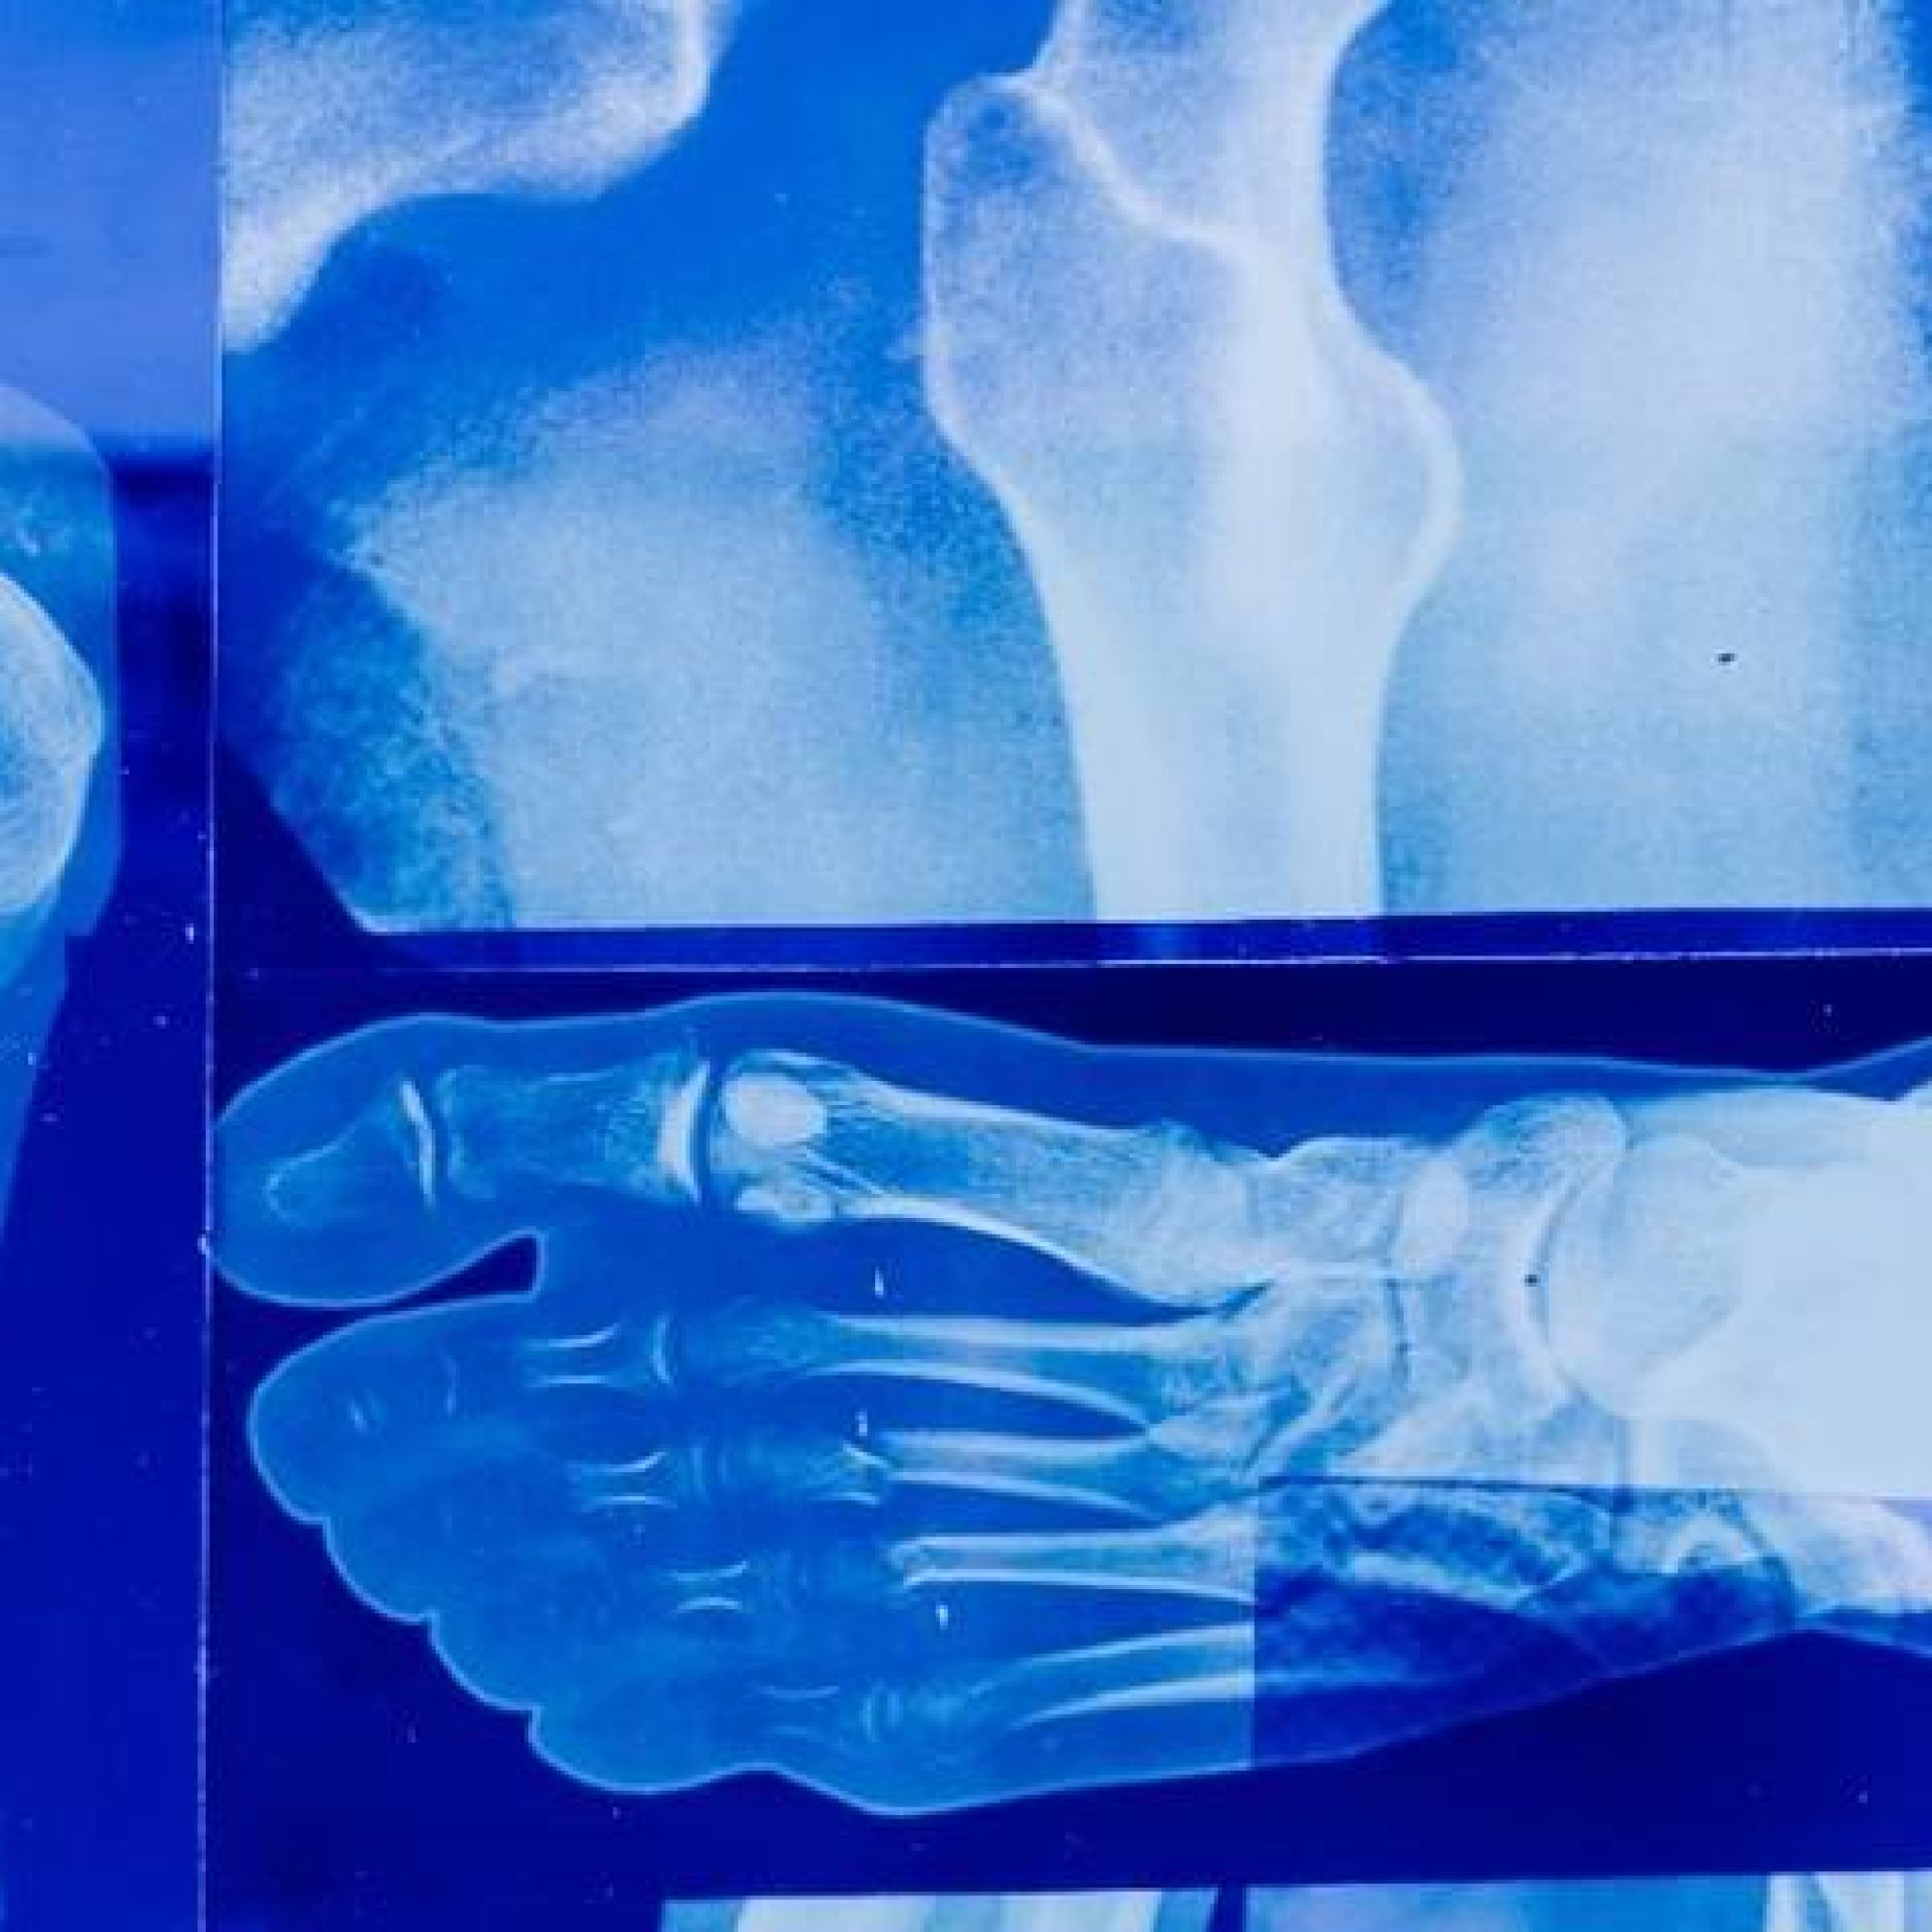

La mala calidad ósea aumenta la fragilidad, riesgo de fracturas y de osteoporosis

El encargado de la Jefatura de Prestaciones Médicas del IMSS en Chihuahua, doctor José Daniel Figueroa Alonzo, informó que 6 de cada 10 personas tienen mala calidad ósea, lo que aumenta la fragilidad y riesgo de fracturas, por lo que exhorta a llevar a cabo medidas preventivas para evitar osteoporosis y otras complicaciones. Sin embargo, afirmó que esta enfermedad se puede prevenir o bien se puede retrasar su aparición.

Añadió que la osteoporosis es una enfermedad crónica y progresiva que origina una disminución de la masa ósea, con el aumento de su fragilidad y fracturas.